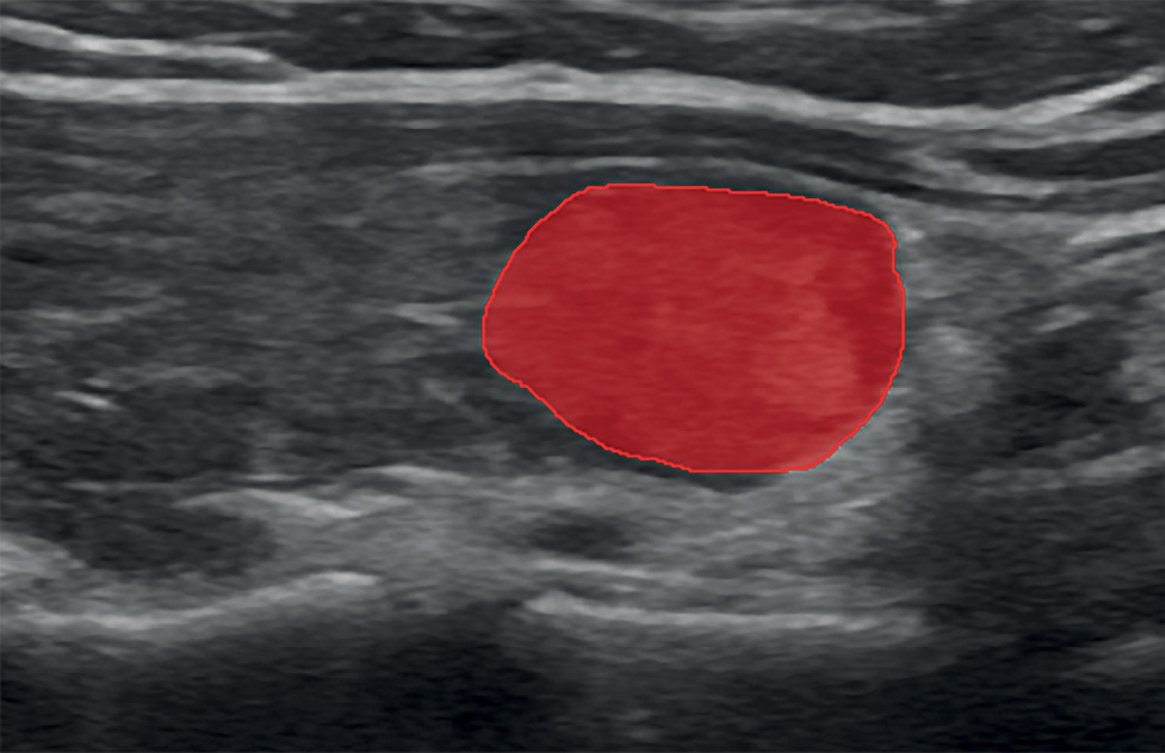

5. Рис. 5. Маска узлового образования щитовидной железы, категория 5 EU-TIRADS. | |